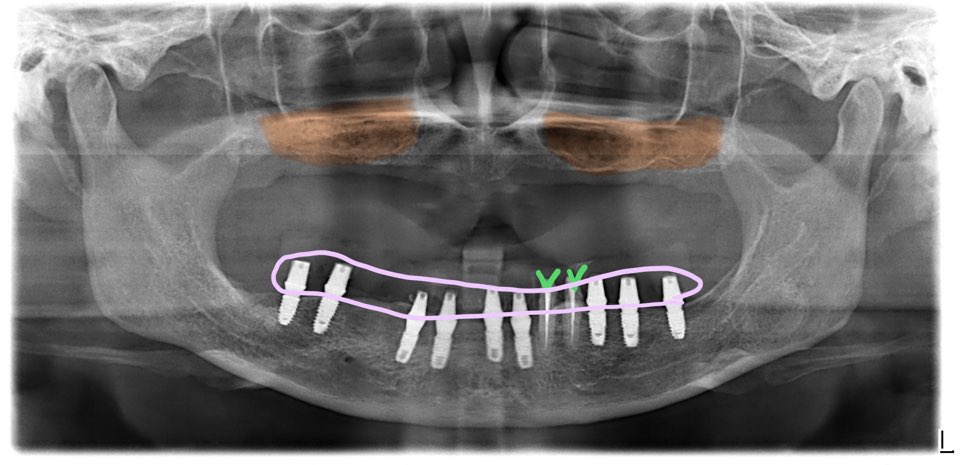

하악은 발치와 동시에 임플란트를 9개 식립했고, 2개의 치아는 예방적 신경치료를 한 후 크라운 프랩을 하고 아래 전체를 묶어서 수술당일 임시치아를 적용했습니다.

하악은 우측부위 보철이 있는 곳은 뼈가 거의 다 무너지고 많이 흔들리는 상태여서 그 부분의 치아들은 제거하기로 했고, 왼쪽에 2개의 치아들은 뿌리 상태가 괜찮아 예방적 신경치료후 보존하기로 결정했어요.